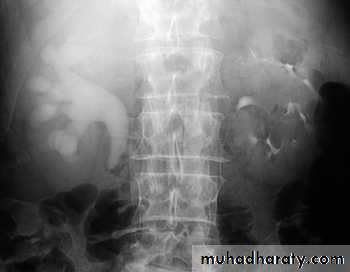

HydronephrosisDilatation of the renal pelvis and calyces with progressive atrophy of the kidney due to chronic incomplete (Partial) obstruction to urine outflow.

With more progressive dilatation → more atrophy of renal parenchyma and kidney become as cystic structure

2. Passage of large stone → impaction at upper or lower end of ureter or pelvic brim → stasis causing hydroureter, hydronephrosis & infection + stasis with further stone formation – stag horn stones